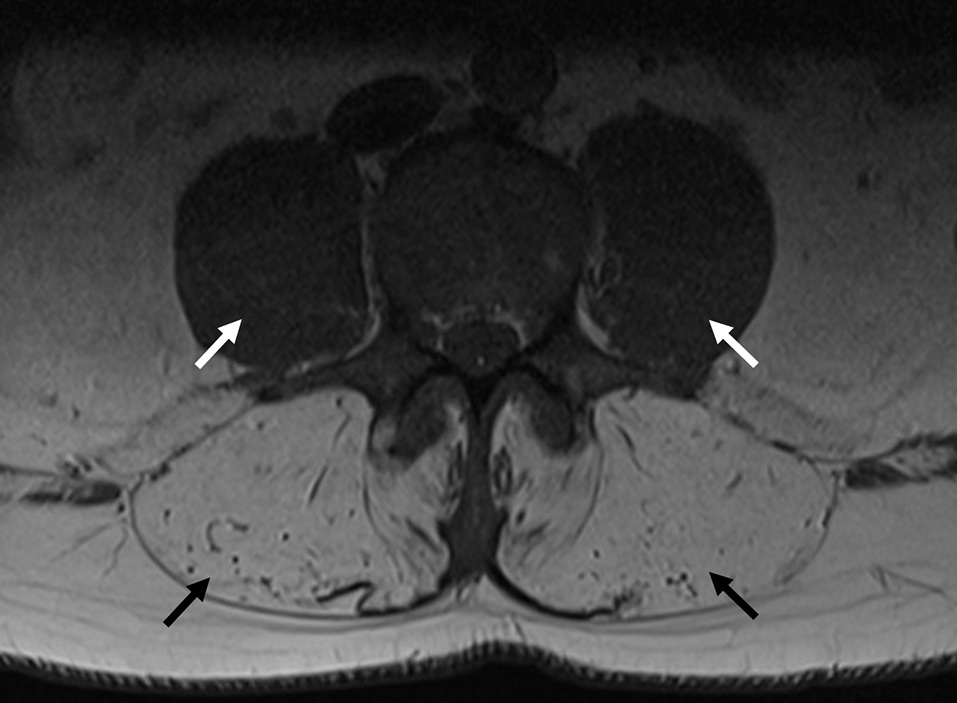

Figure 3

MRI of the lumbar spine from Proband 2. Transverse axial image of a T1 sequence in the lumbar spine, indicating severe paraspinal muscle atrophy (black arrows), with preservation of psoas muscles (white arrows).

The case of Proband 2 emphasizes the value of assessing paraspinal muscles on MRI, since the involvement is a striking feature in this case. This abnormality has been observed in a subset of previously reported cases (12), often in conjunction with atrophic abdominal muscles (13). However, it should be noted that previously described cases with paraspinal muscle involvement had advanced disease, while the case of Proband 2 had this finding as an early and prominent feature of his clinical presentation. This finding is not mentioned in expert reviews of this condition (14, 15), perhaps due to lack of ascertainment or awareness of this abnormality. However, we emphasize this finding for its utility in directing genetic investigation and in genotype-phenotype correlation. Early axial muscle involvement was also reported from one series of GNE myopathy patients, in which one patient had developed early respiratory failure whilst still ambulant (16).